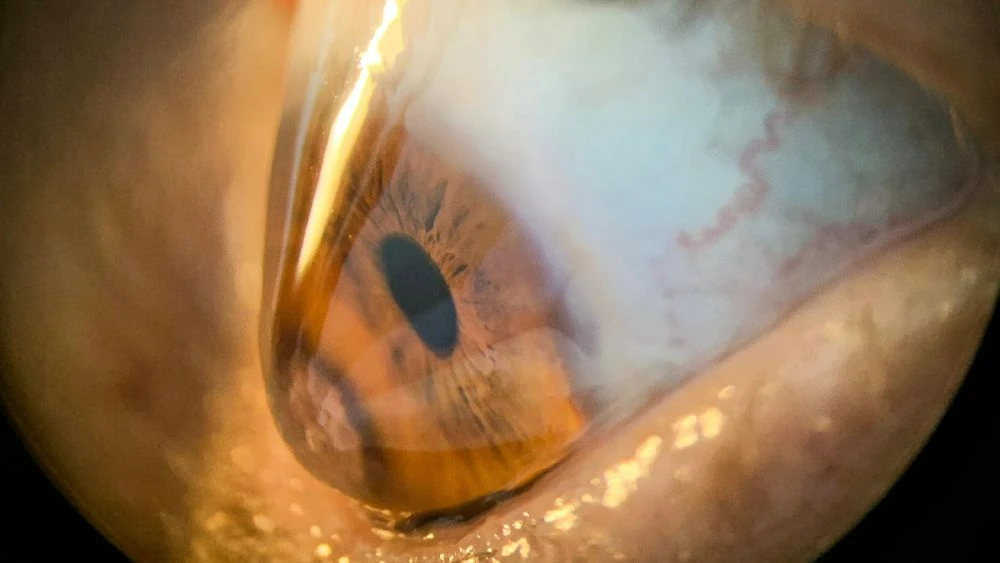

CIRURGIA REFRATIVA E CERATOCONE

Antes de qualquer indicação cirúrgica, realizamos uma avaliação detalhada da saúde ocular. Fazemos exame completo no consultório e solicitação de exames necessários. A decisão não é baseada apenas no grau. É baseada na segurança estrutural da córnea.

A cirurgia não causa ceratocone, mas pode haver risco de ectasia em paciente com predisposição natural. Por isso, a avaliação da córnea com exames avançados é essencial antes da indicação.